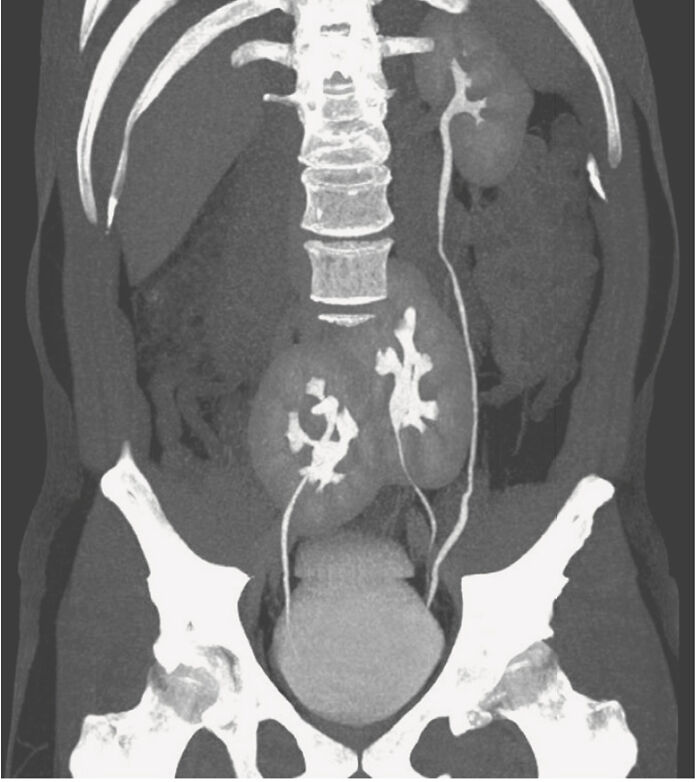

Three Kidneys Discovered In A Man! - Medical Case

Sounds like someone is meant to be a kidney donor. I hope he considers it!